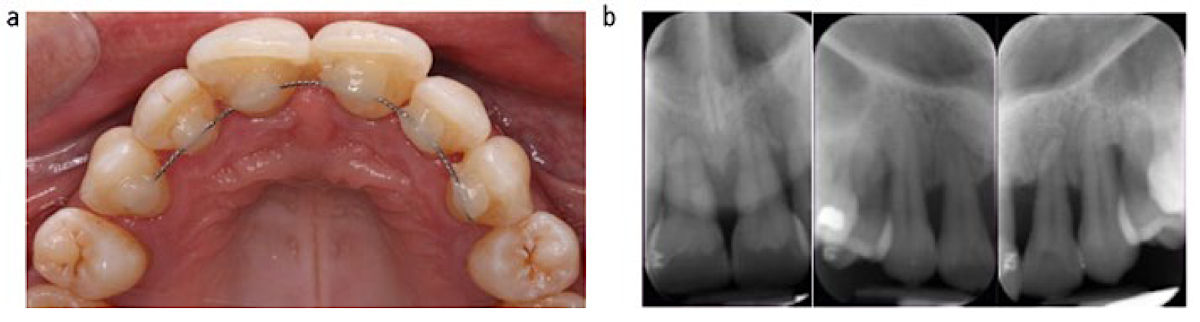

Фото 2. (a) Тяжёлый случай пародонтита с дуговой шиной и композитом; (b) Рентгенограммы до лечения